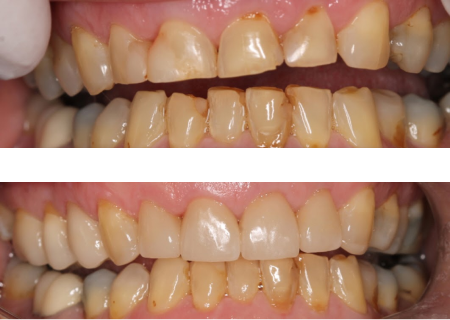

Changes in bite position with comprehensive treatment

When there is insufficient space to restore teeth

Opening the bite position provides a more stable

position also protecting the front teeth

Original bite position

Opened bite with upper restorations